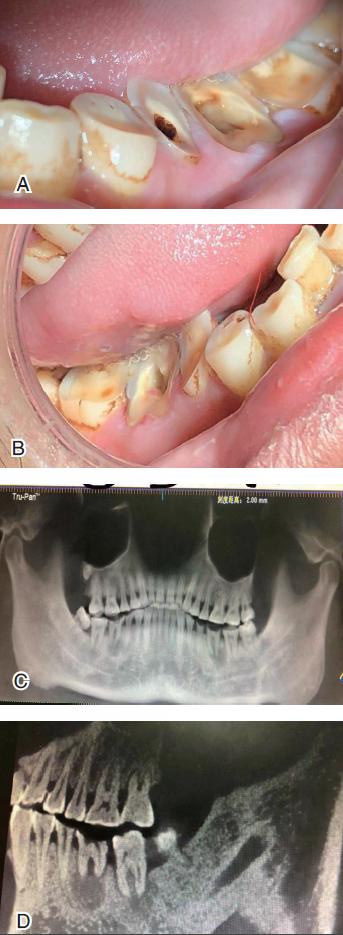

当咀嚼这些槟榔一段时间后,槟榔果实就变成槟榔纤维。这种纤维对口腔黏膜有严重的刺激性。咀嚼时间较长后,口腔的不同策划和器官就会出现不同的病变,如牙齿和牙齿周围策划的病变(图3)、黏膜和颌骨的病变以及颞下颌关节的病变。

长时间咀嚼槟榔会导致上下颌牙齿的磨耗,尤以上下颌前磨牙和磨牙的磨耗最为明显。牙齿的磨耗临床上表现为牙冠颊侧的磨耗较舌腭侧为重。如有牙冠髓腔暴露的情况,可导致急性牙髓炎,长久后可导致慢性牙髓炎的症状和临床表现。如果此时不治疗,就可能进一步发展成为残根。这时,如果不将残根拔除,就会导致残根根尖周围炎甚至导致颌骨囊肿或颌骨骨髓炎(见下文图4)。

近期,有一34岁的槟榔咀嚼者,发现自己的张口度变小,上下颌的磨牙严重磨耗,吃冷热食物及喝凉水时疼痛明显,来湘雅医院口腔医学中心就诊。接诊医师经检查后发现,上下颌磨牙牙严重磨耗,尤以下颌磨牙最为突出,有牙神经外露;患者的张口度为25 mm,双颊及软腭黏膜苍白,有纤维条束存在。双侧面部为方形脸。CBCT检查发现双侧磨牙呈斜形磨耗,疑似残根,根尖有圆形暗影(图4)。最后诊断为:1.中度口腔黏膜下纤维性变;2.上下颌磨牙严重磨耗伴牙髓炎;3.下颌磨牙慢性牙根尖周围炎;4.下颌磨牙残根;5. 继发性张口受限。将患者分别转入相关科室治疗。

图4 34 岁的槟榔咀嚼者的牙齿严重磨耗、根尖病变、下颌角及颞颌关节的位置情况